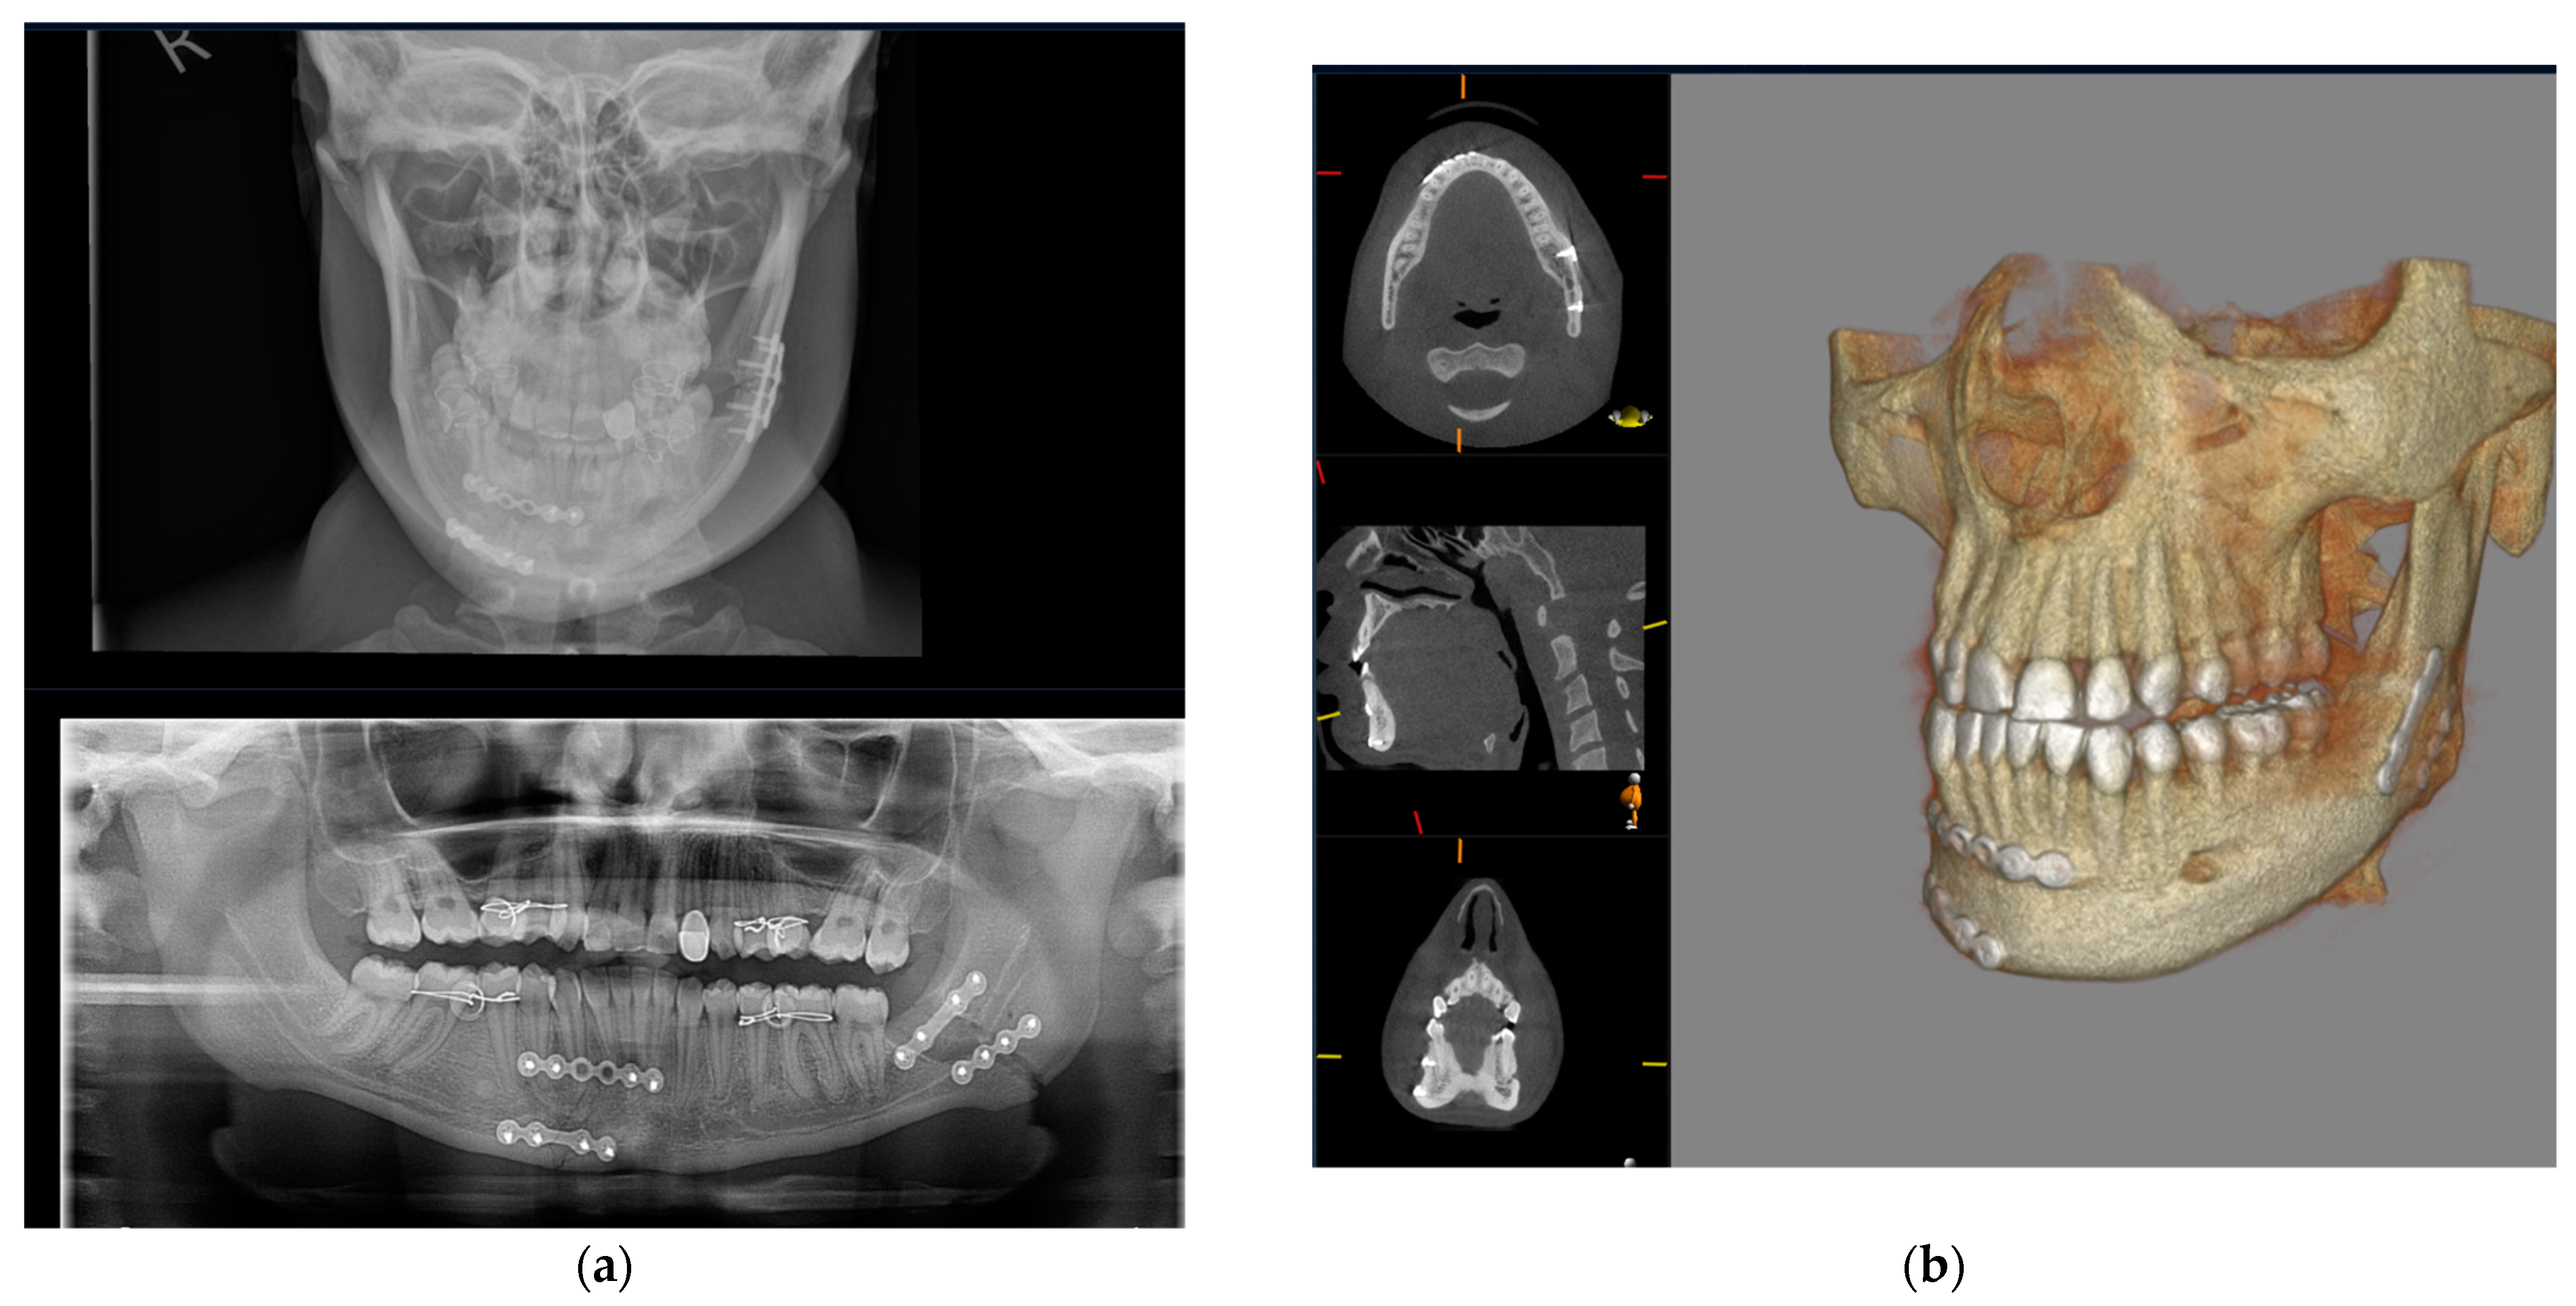

The zygoma is the second-most commonly fractured facial fracture after nasal bone fractures. It contributes to the structure of the midface, articulating with several bones of the craniofacial skeleton, and thus fractures can be associated with significant functional and aesthetic morbidity. In the last decade, conventional CT has replaced occiptomental plain radiographs as the gold standard for imaging assessment. The ability to review imaging in multiple planes can aid the surgeon in understanding the direction of displacement to plan the reduction and fixation required for stability. Figure 6 demonstrates the difficulties with interpreting OM views owing to the superimposition of anatomical structures. The left zygomatic complex fracture is much better visualised on CBCT-reconstructed images.

Figure 6.

Occipitomental views and CBCT axial, sagittal, coronal, and 3D reformatted images demonstrating a fracture to the left zygomatic complex. Conventional occipitomental views are difficult to interpret owing to superimposition. CBCT-reformatted images show the comminuted nature of the fracture and also allow for visualization of the orbital floor.

Similarly, midface fractures comprising a Le Fort Pattern are best appreciated with cross-sectional imaging. These fractures often accompany a multi-injured patient, and thus conventional CT is more readily utilised in non-ambulatory and comorbid patients. Otherwise, CBCT can show a larger number of fracture lines and fragments [40], and 3D printing can facilitate surgical planning, the alignment of teeth, and the construction of custom arch bars without the need for impressions. In our unit, CBCT is often utilised to assess fracture reduction post fixation (Figure 7). This serves as a baseline post-operative image and a more reliable assessment of bone reduction than a plain X-ray.

Figure 7.

Pre-operative CT 3D volume renders and post-operative CBCT axial, sagittal, coronal slices, and 3D volume render showing reduction and fixation of fractures through the symphysis mandible, Le Fort 1 level, and maxillary alveolar bone.